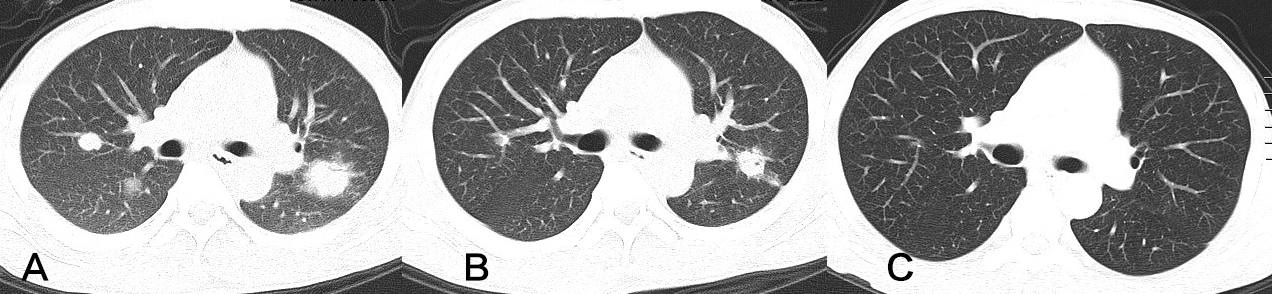

Voriconazole (VRC) is a broad-spectrum triazole antifungal drug and first-line choice for invasive pulmonary aspergillus (IPA) even in patients with liver failure. But it is limited when used in these individuals due to hepatoxicity and supratherapeutic trough plasma concentrations that could lead to severe adverse events appear or aggravate.